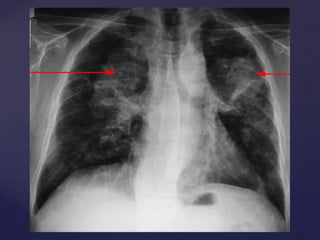

Pneumoconiose  silicose

Doenças causadas

POEIRAS Mineral SiO2 Amorfa ou cristalizada  quartzo, tridimita, cristobalita e trípoli Pneumoconiose  silicose Sílica